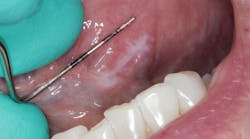

Patient: 27-year-old male

- Chief complaint: upper right tooth, third from the back, was bothering the patient progressively over the last few months

- Patient has slightly elevated blood pressure and is a chronic tobacco user

- Rough, corrugated-cardboard-like tissue in large area of lower left vestibule

- Patient is aware of the risks associated with tobacco